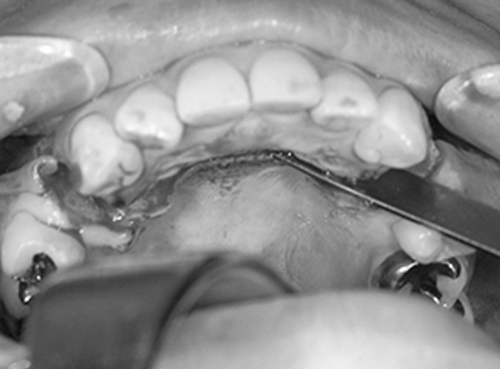

4. 切開をします

手術を始めます。

骨を削って、後ろに下げるために必要な範囲を切開します。

抜歯をした歯の部分に縦に1cmくらいの小さな切開をします。粘膜のみを切開し、他の組織を損傷しません。切開には15番メスや電気メスを使用します。切開面からガーゼを使って優しく手指ではがすと、骨の幕である骨膜が見えてきます。骨を切ったり、削ったりする部分だけを露出します。

5. 剥離します

剥離(口の中で骨が見える範囲)は、上は隣の歯の根っこまで、内側は小鼻の付近まで、お鼻の粘膜もお口の中から一部をはがしておくと、骨がきれいに切れて、手術後の出血が少なく、腫れも少なく、治りが早くなります。

また、切開と剥離の工夫は、手術が終わって縫う時に、不自然な表情にならないようにするための縫い代の確保につながります。

4. 切開します

下のあごの手術を始めます。骨を切って、削って後ろに下げるために必要な範囲を切開します。下くちびるの裏側に3cmくらいの小さな切開をします。薄い粘膜だけを切開します。

切開にはメスや電気メスを使用して、他の組織を傷つけません。切った部分からガーゼを使って優しく手指で伸ばすと、粘膜の下にオトガイ筋、下唇下制筋、オトガイ神経などが透けて見えます。傷つけないように慎重に次の作業に進みます。